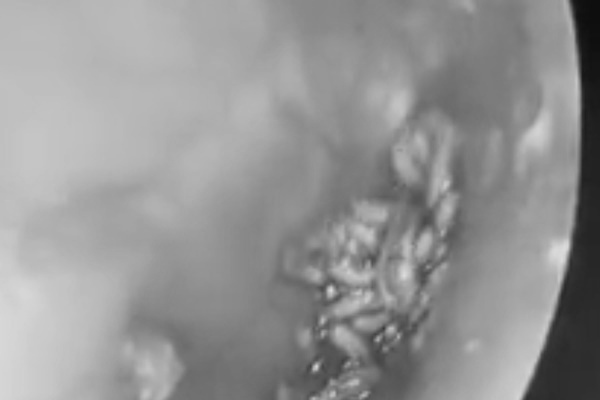

Những con giòi được gắp ra từ tai phải của bệnh nhân T

Đến Bệnh viện Tai Mũi Họng Trung ương, khi nội soi, các bác sĩ phát hiện nhiều dị vật màu trắng di động là những con giòi lúc nhúc lấp đầy hòm nhĩ của bệnh nhân T. Các bác sĩ đã gắp ra hơn chục con giòi tại chỗ, tuy nhiên, do ống tai sưng nề, chít hẹp nên còn rất nhiều giòi chưa thể xử lý hết. Do đó, bệnh nhân được chỉ định tạm thời điều trị nội khoa, tiêm truyền kháng sinh, kê thuốc giảm viêm.

Ngày hôm sau, các bác sĩ đã thực hiện phẫu thuật nội soi, tiếp tục gắp hàng chục con giòi ra và vét sạch tổ chức viêm trong tai giữa của bệnh nhân. Hiện tại, tình trạng tai của người bệnh đã ổn định và đã được xuất viện.